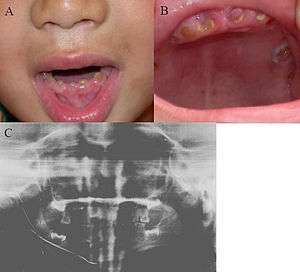

Dentinogenesis imperfecta (DI) is a genetic disorder of tooth development. This condition is a type of dentin dysplasia that causes teeth to be discolored (most often a blue-gray or yellow-brown color) and translucent giving teeth an opalescent sheen.[1] Teeth are also weaker than normal, making them prone to rapid wear, breakage, and loss. These problems can affect both primary (deciduous) teeth and permanent teeth. This condition is inherited in an autosomal dominant pattern, which means one copy of the altered gene in each cell is sufficient to cause the disorder. Dentinogenesis imperfecta affects an estimated 1 in 6,000 to 8,000 people.

Clinical appearance is variable. However, the teeth usually involved and more severely affected are primary teeth in type I; whereas in type II both the dentitions are equally affected.

The teeth may be gray to yellowish brown. They exhibit translucent or opalescent hue. Enamel is usually lost early due to loss of scalloping at the dentoenamel junction (DEJ). However, the teeth are not more susceptible to dental caries than normal ones.

However, certain patients with dentinogenesis imperfecta will suffer from multiple periapical abscesses apparently resulting from pulpal strangulation secondary to pulpal obliteration or from pulp exposure due to extensive coronal wear. They may need apical surgery to save the involved teeth.[3]

Radiographic features

Type I and II show total obliteration of the pulp chamber.

Type III shows thin dentin and extremely enormous pulp chamber.These teeth are usually known as "shell teeth".